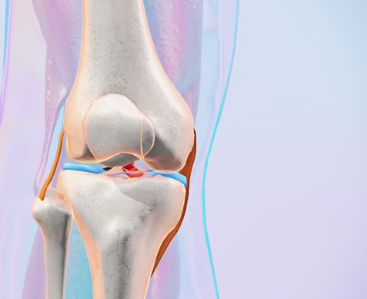

1. 무릎 연골 손상이란 무엇인지부터 쉽게 이해하기

무릎에는 뼈가 서로 부딪히지 않도록 도와주는 “연골”이 있어요.

대표적으로 두 가지가 중요합니다.

첫째, 관절연골

무릎뼈 끝을 매끈하게 감싸서 마찰을 줄여주고 충격을 흡수해요.

둘째, 반월상연골(반달연골)

무릎 안쪽과 바깥쪽에 있는 반달 모양의 연골로, 체중이 한쪽에 쏠리지 않도록 분산해 주는 역할을 해요.

이 연골이 닳거나 찢어지거나 손상되면 무릎이 뻣뻣하고 아프고, 걷는 자세까지 달라지면서 다른 관절까지 무리가 가기 쉬워요.

연골은 혈관이 거의 없어서 “피가 통하면서 빨리 낫는 조직”이 아니에요. 그래서 작은 손상도 그냥 넘기지 말고, 초기에 관리해 줘야 회복이 훨씬 수월합니다.